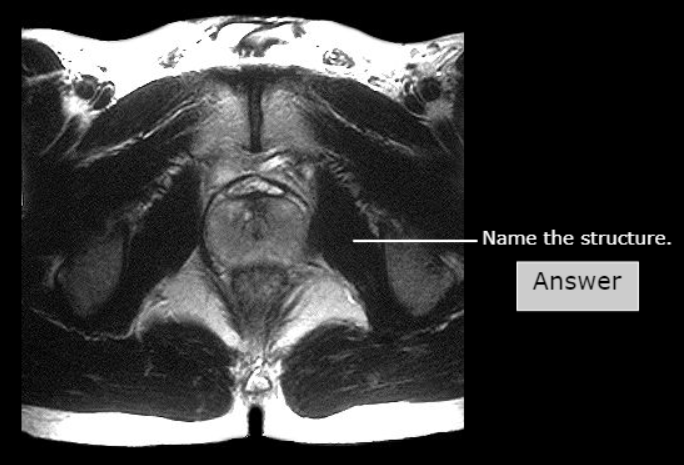

Pelvic Diaphragm